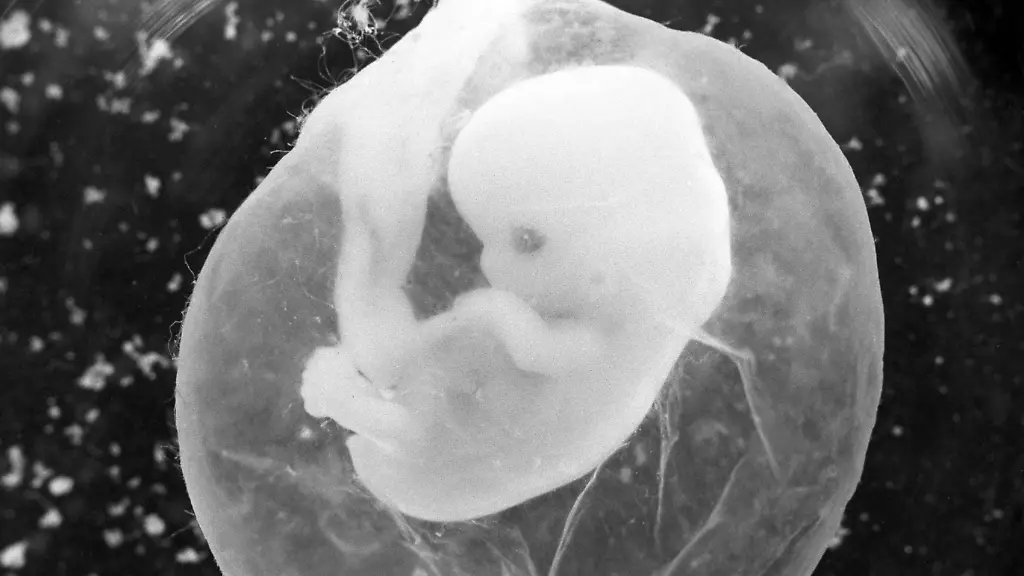

Organoide aus Zellen von FötenWie Mini-Organe aus Fruchtwasser gezüchtet werden

Mini-Versionen von Lunge, Darm, Herz und Co: Organoide sind künstlich erzeugte 3D-Zellkulturen, die ausgewachsenen Organen sehr ähnlich sind. Sie versprechen medizinischen Fortschritt, sind allerdings aufwendig in ihrer Herstellung. Jetzt ist es Forschenden gelungen, Organoide aus Zellen im Fruchtwasser zu züchten.

Es klingt wie Science-Fiction: Labore weltweit züchten schon seit Längerem Organe in Miniaturausgabe, um daran die Funktionsweise, aber auch Organdefekte zu erforschen. Die sogenannten Organoide sind nur wenige Millimeter groß, aber den ausgewachsenen Organen sehr ähnlich und weisen vergleichbare Merkmale auf. Sie entstehen bislang aus umprogrammierten Körperzellen. Jetzt ist es Forschenden jedoch gelungen, erstmals Organoide aus Zellen im Fruchtwasser zu züchten.

Dass sich im Fruchtwasser etliche Zellen befinden, die vom Fötus stammen, ist bekannt. Wissenschaftlerinnen und Wissenschaftler der University College London haben diese nun genauer untersucht, wie sie im Fachmagazin "Nature Medicine" berichten. In einem ersten Schritt trennten sie die lebenden von den abgestorbenen Zellen, welche sie dann mithilfe von Einzelzellanalysen sequenzierten und charakterisierten. So fanden sie gewebespezifische Stammzellen der obersten Zellschicht des Magen-Darm-Trakts, der Nieren und der Lunge des Fötus. In einem weiteren Schritt ließen sie diese Vorläuferzellen in 3D-Kulturen zu Organoiden heranwachsen, die funktionelle Merkmale ihres Ursprungsgewebes aufwiesen.

Diese Zellkulturen wiesen vergleichbare Merkmale zu den Organen des heranwachsenden Kindes auf, heißt es in der Studie. So konnten die Forschenden Lungenorganoide von Föten mit angeborenem Zwerchfellbruch erzeugen. An diesen wollen sie nun erforschen, wie und warum sich die Entwicklung der erkrankten Lungen von Gesunden unterscheidet. Davon erhoffen sie sich neue Therapiemöglichkeiten.